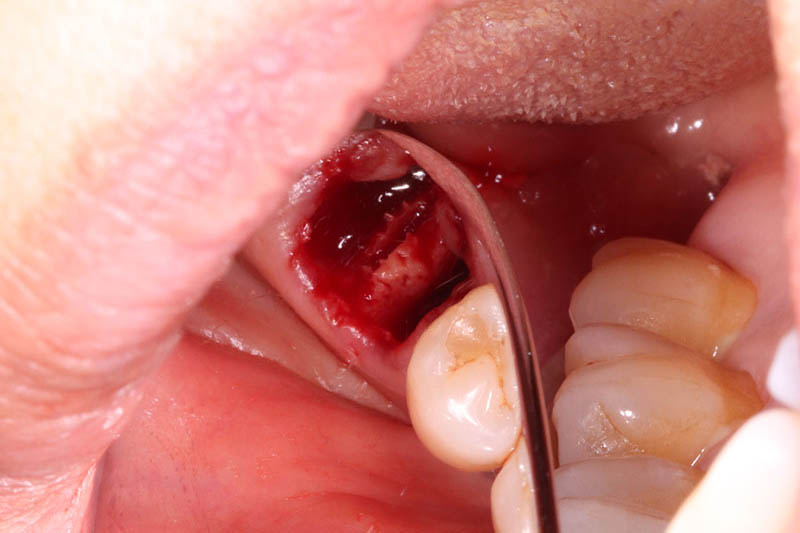

残根抜歯とPRGFを使用した抜歯窩の保存

コラムを拝見してくださっている方は根っこだけだから簡単に抜歯できると思われがちかもしれませんが、そうはいきません。むしろ根っこだけの状態の方が抜歯は難しくなります。何故なら歯を抜く時に使用する鉗子(歯を引っ張って抜くためのペンチみたいな器具のこと)で掴むことが困難だからです。もし鉗子で掴むところがなければ根っこが埋まっている周囲の骨を削らないといけないです。周囲の骨を削ると抜歯後に骨が目減りするのでインプラントを行う際に不利になる可能性があるので、なるべく削らないようにします。このような時当院では図で示したような特殊な道具を使用します。この道具を使用して根っこを引っ張り出すように抜歯するので、周囲の骨を削る必要がありません。今回は特殊な道具を使用して抜歯できたのでよかったのですが、この道具を使用しても抜歯できない場合がありますので、その際は周囲の骨を削って抜歯するしかありません。

この道具なかなか高価なので持っている歯科医院さんが少ないのですが、自称抜歯専門としては持っておかなかればならないと思ったので思い切って購入しました。笑

またインプラント症例①でも行ったように抜歯窩の保存をするために、抜歯時にPRGFを抜歯窩に充填しました。